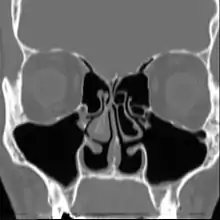

| Altered nasal anatomy after bilateral subtotal inferior turbinectomy, the removal of most turbinate tissue. | |